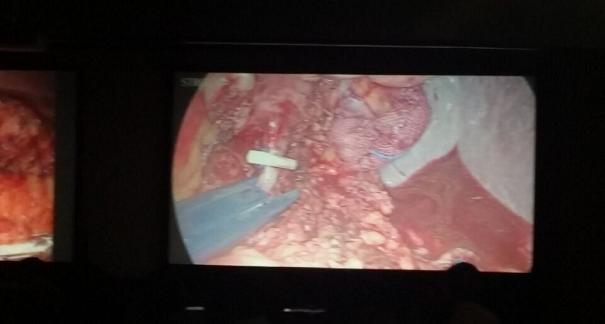

2015年10月23-25日,河北省醫(yī)學會肝膽外科學術(shù)年會在河北省石家莊市頤園賓館隆重召開。本次學術(shù)會議河北省醫(yī)學會特邀了北京301總院的胡明根教授、天津第一中心醫(yī)院的張雅敏教授、山西醫(yī)大醫(yī)院的趙浩亮、河北醫(yī)科大學第二醫(yī)院劉建華教授等國內(nèi)知名專家參會。參加會議的醫(yī)院達100余家,近300名肝膽外科的臨床專家和一線醫(yī)生們親臨會場,在此進行廣泛的學術(shù)交流。25號全天會議安排了五臺手術(shù)視頻演示,全體參會人員進行觀摩,并實時提問,進行手術(shù)交流。演示手術(shù)包括腹腔鏡胰、十二指腸切除術(shù)、腹腔鏡左、右半肝切除術(shù)、腹腔鏡門脈高壓癥的治療、兩鏡或三鏡聯(lián)合膽石癥的治療、開腹胰、十二指腸切除術(shù)、手術(shù)演示中多次使用了我公司產(chǎn)品速豐(可吸收止血結(jié)扎夾),產(chǎn)品使用滿意度受到專家們的一致好評。